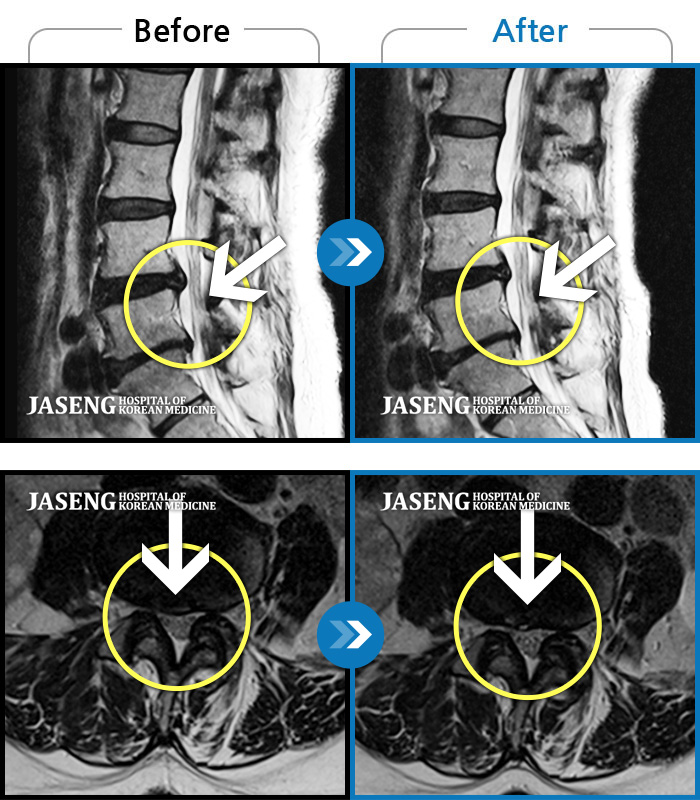

허리디스크

목동 · 고웅 원장

심한 왼쪽 엉치 통증. 종아리, 발바닥 저림

촬영시기

2020.10.14 ~ 2024.10.07

2024.12.24